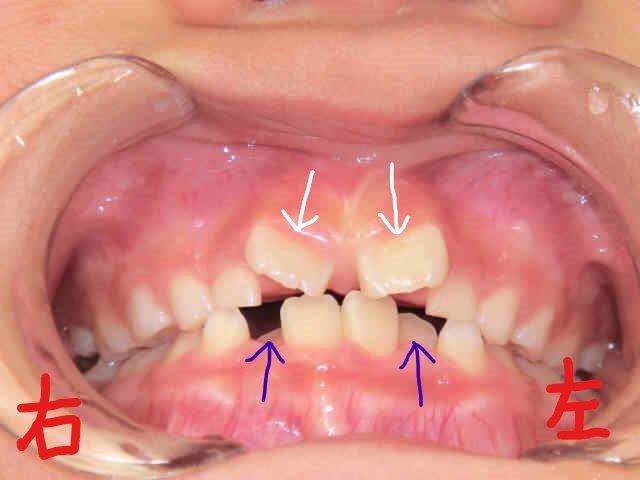

2017年2月、8歳の女の子が「歯並びが気になる」ということで、お母さまとご一緒に矯正相談へご来院されました。左上が正面からの写真、右上が下から見上げた写真です。下顎前歯(青色矢印の歯)がかなり内側に傾き、上顎前歯(白色矢印)が八の字状に生えている状態でした。